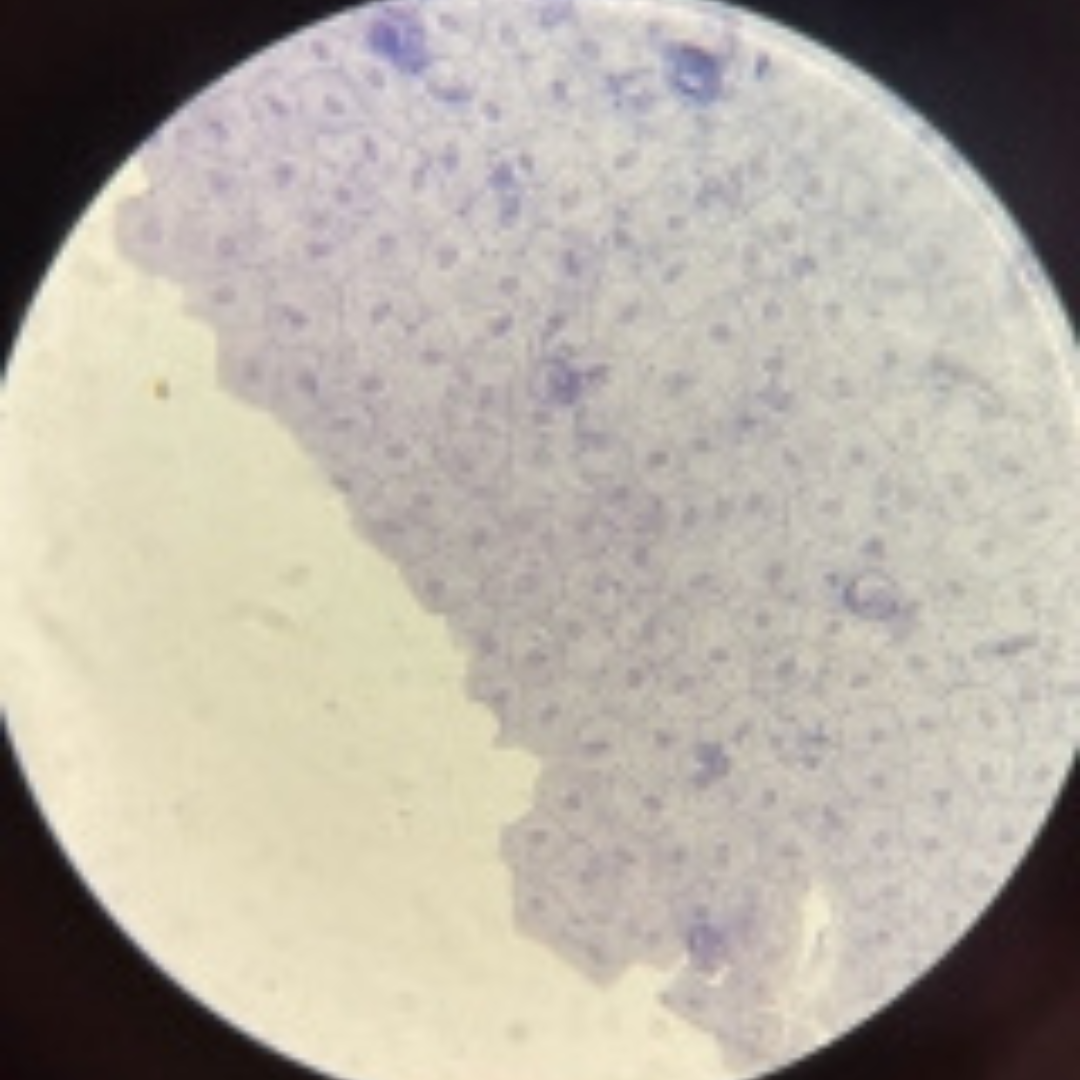

Kidneys (Nephron)

Kidneys (Nephron)

Kidneys (Nephron)

Kidneys (Nephron)

Kidneys (Nephron)

Kidneys (Nephron)

Kidneys (Nephron)